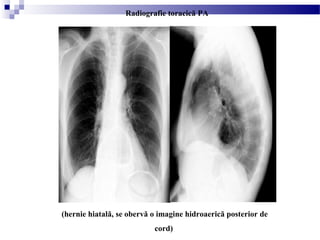

(hernie hiatală, se obervă o imagine hidroaerică posterior de

cord)

Radiografie toracică PA